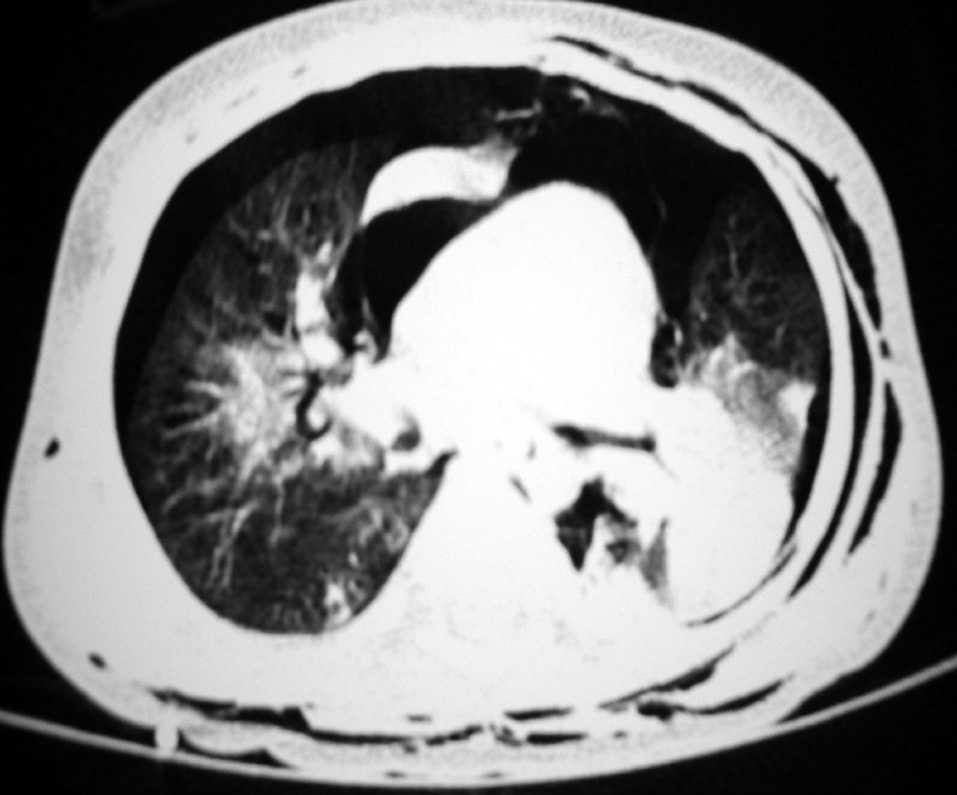

Presentamos el caso de un lactante de 15 meses sin antecedentes de interés, que presentó un cuadro de insuficiencia respiratoria aguda y progresiva tras la aspiración de un producto químico compuesto por hidrocarburos alifáticos de cadena larga. La radiografía de tórax mostraba un infiltrado alveolointersticial bilateral. Se decidió su ingreso y tratamiento con oxígeno, antibióticos y corticoides. En las siguientes 4 h desarrolló un enfisema subcutáneo cervical. La TC de tórax evidenció una consolidación alveolar en ambas bases, neumotórax bilateral, neumomediastino y enfisema subcutáneo (fig. 1). Ante el rápido deterioro clínico del paciente se decidió su traslado a nuestro centro. Aunque a su llegada presentaba una dificultad respiratoria moderada y mantenía una oxigenación normal con oxígeno a través de mascarilla facial, presentó un deterioro clínico e hipoxemia progresivos, por lo que se evacuó el neumotórax derecho y se inició ventilación no invasiva en modo CPAP, sin mejoría evidente (saturación de Hb entre 88 y 92 % a pesar de 10 cmH2O en CPAP y fracción inspiratoria de oxígeno de 0,9). Se decidió entonces la intubación endotraqueal y ventilación mecánica convencional en modo SIMV-P (PIP 35 cmH2O, PEEP 9 cmH2O, FiO2 0,80). El índice de oxigenación calculado una hora después era de 28, observándose en la radiografía de tórax signos de síndrome de distrés respiratorio agudo, por lo que se decidió aplicar la VAFO con los siguientes parámetros iniciales: Paw: 30 cmH2O, ΔP: 92 cmH2O, frecuencia: 11 Hz y FiO2: 0,70. Doce horas después, ante la imposibilidad de disminuir de forma significativa los parámetros ventilatorios, se decidió administrar surfactante pulmonar. Unas 12 h más tarde comenzó a objetivarse una mejoría de la oxigenación (fig. 2) que permitió iniciar el descenso progresivo de los parámetros ventilatorios. El niño se mantuvo con VAFO durante 10 días y se extubó tras 24 h de transición ventilación convencional, sin otras incidencias.

Figura 2. Evolución del índice de oxigenación del paciente.